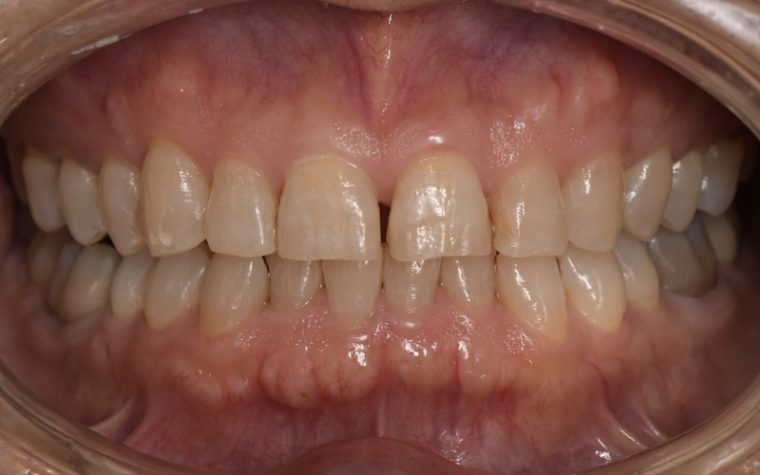

Before

| 主訴 | 歯石を取りたい |

| 治療内容 | 超音波スケーラーでの歯石除去 |

| 治療期間 | 60分 |

| 治療費 | 初診料を含め約4,500円 |

| リスク・副作用 | 歯ぐきに違和感や痛みを覚える場合がある。 1週間程度、歯を磨くといつもより出血することがある。 腫れていた歯ぐきが引き締まることで歯ぐきが下がった様に見える。 歯ぐきが下がることで歯がみしやすくなることがある。 一時的に歯の動揺(ゆれ)が増す場合がある。 |